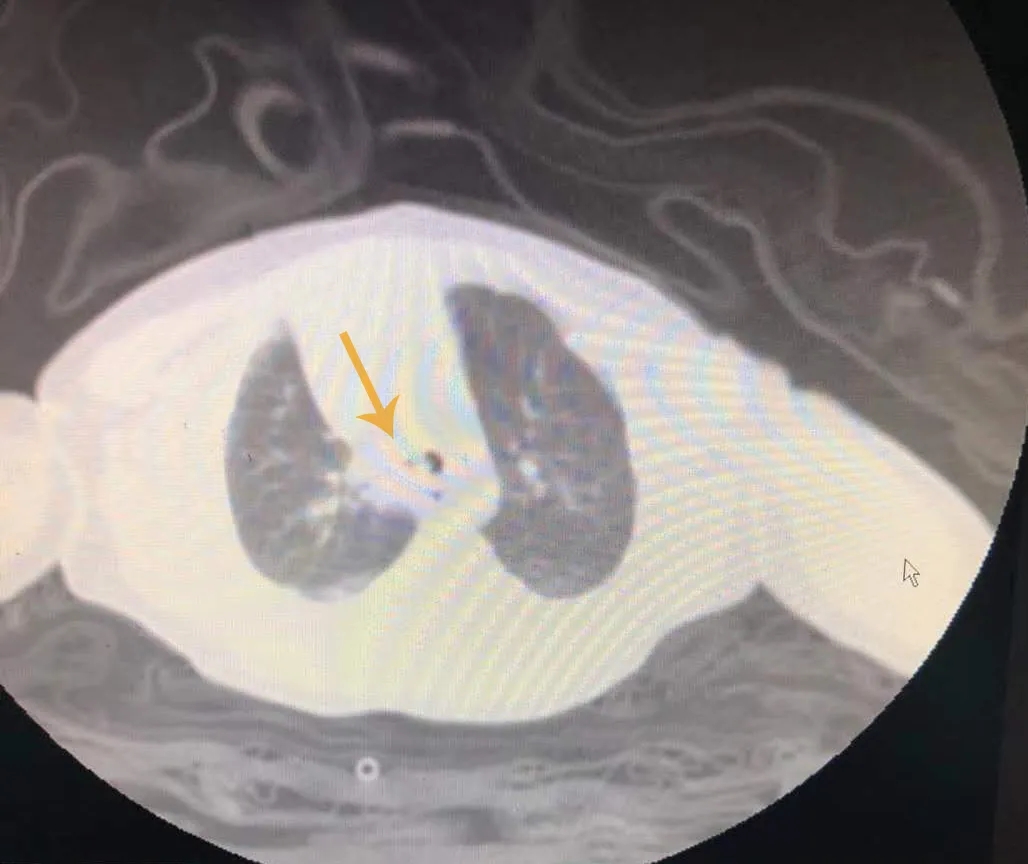

转入我院后,小华出现呼吸困难加重、紫绀,医生立即予气管插管、呼吸机辅助呼吸。同时结合床边DR与外院胸部CT,发现小华右肺不张,气管有高密度增高影,高度怀疑其主气管内有异物且非家属说的可能是米糊类食物,但小华家属否认喂食过米糊或牛奶以外的食物。

(外院CT检查显示患儿气管内有异物)